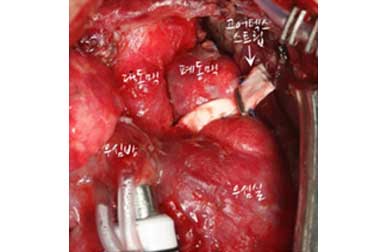

(1) 폰탄수술 후의 모습

폰탄수술 후의 모습